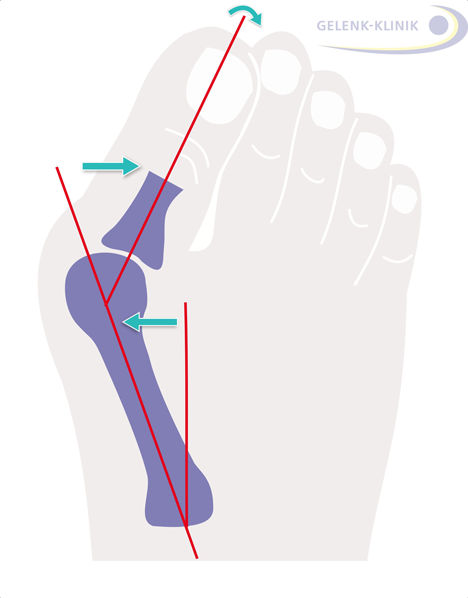

Durch den Zug der Sehnen dreht sich der Großzeh bei einem Hallux valgus aus dem Großzehengrundgelenk heraus – ähnlich wie ein gespannter Bogen. Er neigt sich nach außen, in Richtung der anderen Zehen. Der einwärts gedrehte Großzeh verdrängt die Zehen, wodurch diese ebenfalls eine Fehlstellung annehmen. Ein Hallux valgus tritt daher oft in Verbindung mit Hammerzehen oder Krallenzehen auf.

Rolle der Sesambeine bei Hallux valgus

In der Sehne des kurzen Großzehenbeugers (Musculus flexor hallucis brevis) sind zwei Sesambeine eingebettet. Diese kleinen Knöchelchen fungieren als Gleitlager und verstärken die Kraftwirkung des Muskels. Sie liegen unter dem Großzehengrundgelenk und nehmen normalerweise den 1. Zehenstrahl in ihre Mitte.

Beim Hallux valgus sind diese Sesambeine nach außen verschoben. Es entsteht ein Winkel zwischen dem Verlauf des Großzehenstrahls und der Sehne des Zehenbeugers. Je größer dieser Winkel ist, desto ausgeprägter ist die Hallux valgus-Fehlstellung.

Weichteileingriffe: Behandlung von Sehnen und Gelenkkapsel an der Großzehe

Die Kapsel um das Großzehengrundgelenk hat sich durch die Fehlstellung bereits so verengt, dass die Fehlstellung kontrakt, also nicht mehr aktiv durch den Patienten zurückführbar ist. Auf der Seite des Knicks im Großzehengrundgelenk (rot) ist die Kapsel überdehnt, auf der Gegenseite ist sie verkürzt. Um die Großzehe dauerhaft zu begradigen, löst und erweitert der Fußspezialist die Gelenkkapsel und passt die Länge der Sehnen an, die die Großzehe steuern.